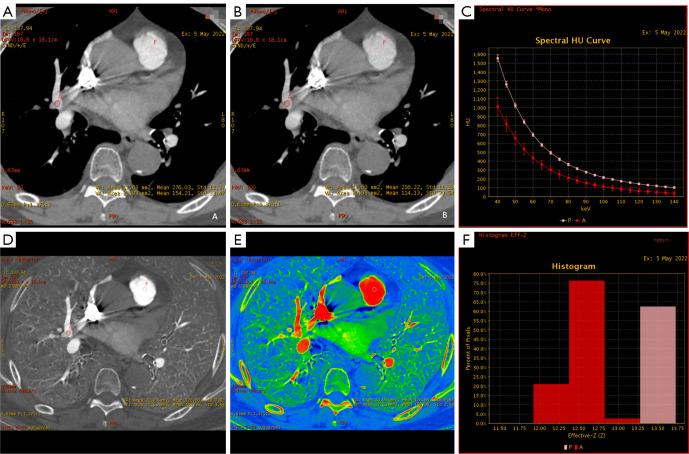

A total of 68 patients with PE who underwent DE-CTPA were retrospectively included. Quantitative parameters [slope of Hounsfield unit (HU) curves (Slope), CT values on virtual monoenergetic images (VMIs) ranging from 40 to 100 keV (HU-HU), normalized iodine concentration (NIC), and normalized effective atomic number (NEffZ)] on the BHA-induced low-density area of the right upper pulmonary artery (artifact), embolism, and the corresponding normal area of the left upper or right middle pulmonary artery (normal) were measured and calculated. The parameters among the three groups were compared, and the performances of the parameters in differentiating the three conditions were evaluated.

Quantitative parameters, including HU, HU, NIC, NeffZ, and Slope were all highest for normal arteries, followed by artifacts, and lowest for embolism (all P<0.05). To differentiate artifact and embolism, all parameters had areas under the curve (AUCs) higher than 0.80 (0.808-0.963), and HU had the highest AUC of 0.963. The multi-variables, combining HU, NIC, and NEffZ, had an AUC of 0.968, comparable to HU (P>0.05). Between normal and artifact, NIC showed the highest AUC (0.865), whereas multi-variables combining HU, NIC, and Slope improved the AUC to 0.937 and the model quality increased to 0.90 (P<0.05). For differentiation between normal and embolism, all parameters had AUCs higher than 0.80 (0.849-0.991); HU and HU showed the highest AUCs of 0.99 and 0.991, respectively. After a multivariable analysis combining HU, NIC, and Slope, the AUC was increased slightly to 0.995, which was comparable to that of HU and HU (P>0.05).

Quantitative parameters derived from DECT could recognize BHA in the superior vena cava; therein, 90 keV and 100 keV VMIs and their HU measurements would be particularly valuable.